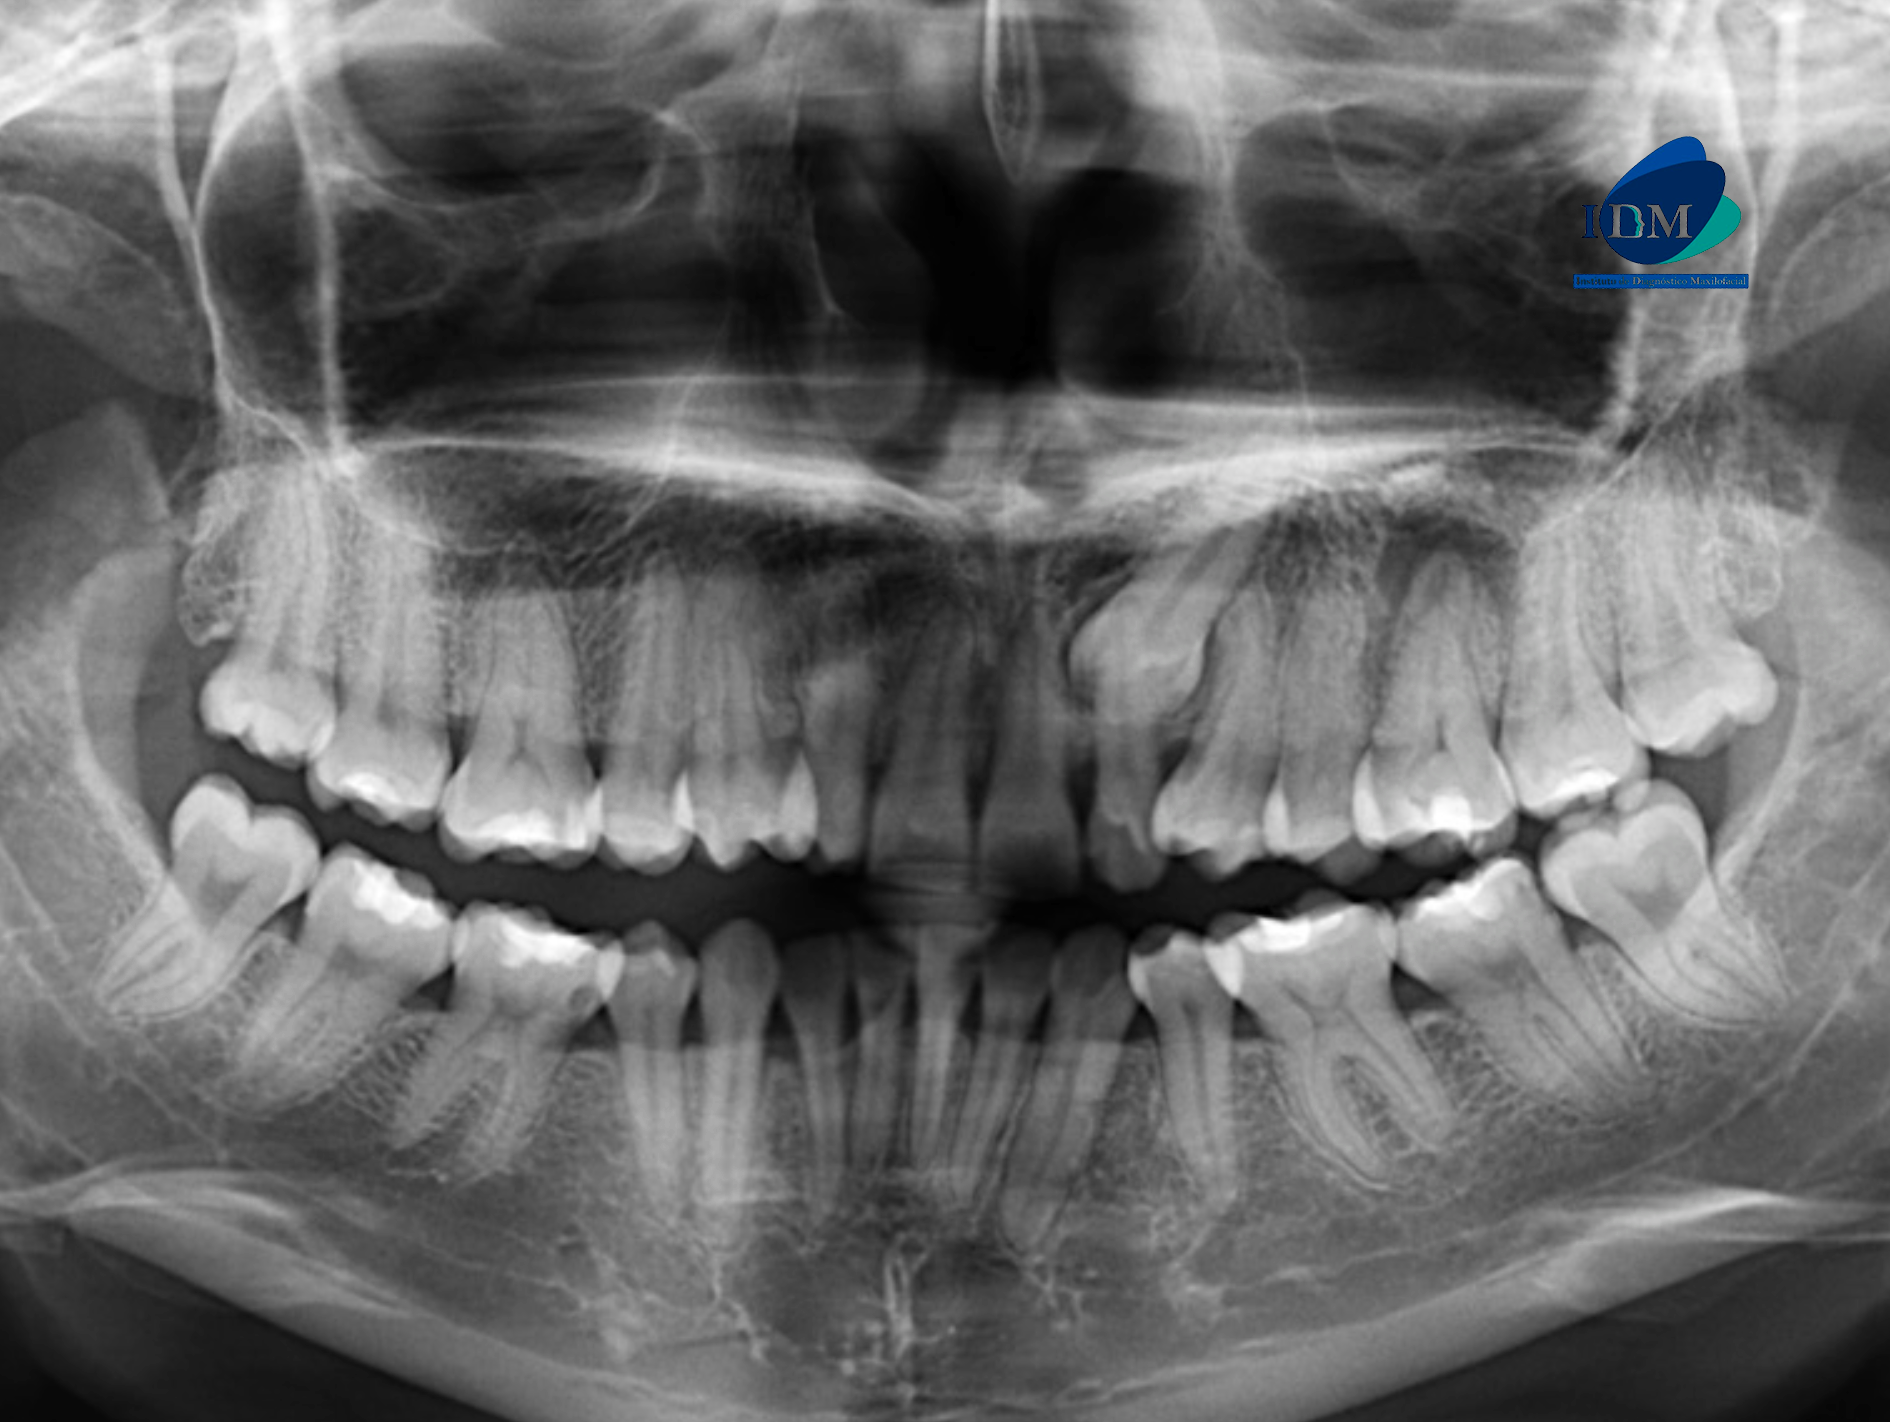

Radiografia Panorámica

A la evaluación de la radiografía panorámica se observa neumatización de ambos senos maxilares, la ausencia de la pieza 13, la alteración de la morfología coronaria de las piezas 14 y 24 compatible con dens evaginatus, asimismo se observa la ausencia de las piezas 34 y 44, la impactación de la pieza 23 y el proceso osteolítico periapical de la pieza 26 proyectado sobre el piso de seno maxilar.